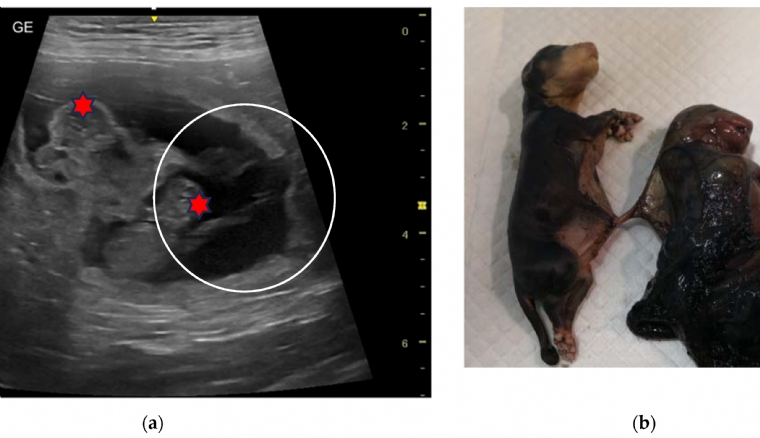

Le diagnostic prénatal comprend un ensemble d'investigations, instrumentales et en laboratoire, qui visent à surveiller la santé du foetus pendant la gestation, depuis les premiers stades du développement embryonnaire jusqu'aux moments précédant la mise b...